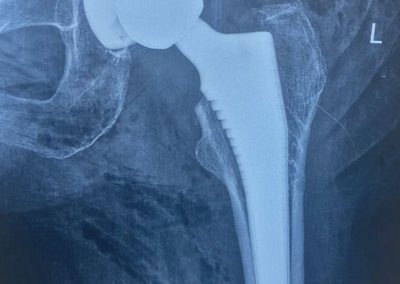

تم إجراء تثبيت داخلي لكسر بالحوض بمسامير عام ٢٠٠٩

في عام ٢٠٢١ بدأت تشعر بالام متزايدة بالمفصل كما بينت الاشعات تآكل به

عام ٢٠٢٤ كانت الالام مع المشي اصبحت شديدة مما استدعى عمل تغيير كامل للمفصل